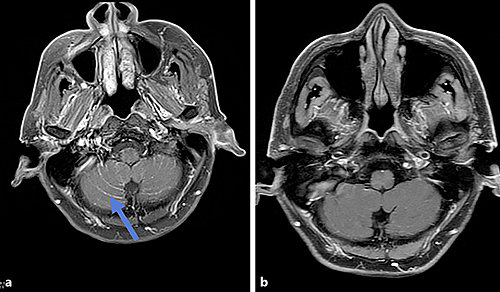

病例报道:男,亚裔,68岁,肺腺癌,骨转移,EGFR L858R突变,最初吉非替尼治疗。一年后,疾病恶化。右下肺叶原病灶活检,无 T790M突变,只有EGFR L858R突变。患者意识混乱,身体疲劳,大脑核磁共振成像(MRI)显示广泛脑转移(图1-a)。液体活检显示EGFR T790M突变。奥希替尼治疗6个月后,MRI结果有明显的改善(图1-b)。不幸的是